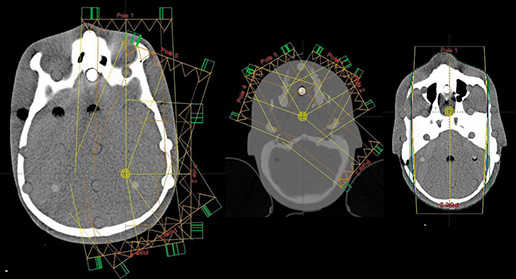

Verification of CT images reconstructed by means of iMAR algorithm within a region of head and neck Streszczenie W artykule poruszono tematykę planowania radioterapeutycznego pacjentów z wszczepionymi endoprotezami, które zaburzają obraz wykonany podczas badania CT. Najczęściej są to protezy główki kości udowych, panewek, rozruszniki serca, expandery po mastektomii czy implanty dentystyczne. Skan z tomokomputera uzyskany w obszarze tych implantów jest w zasadzie…